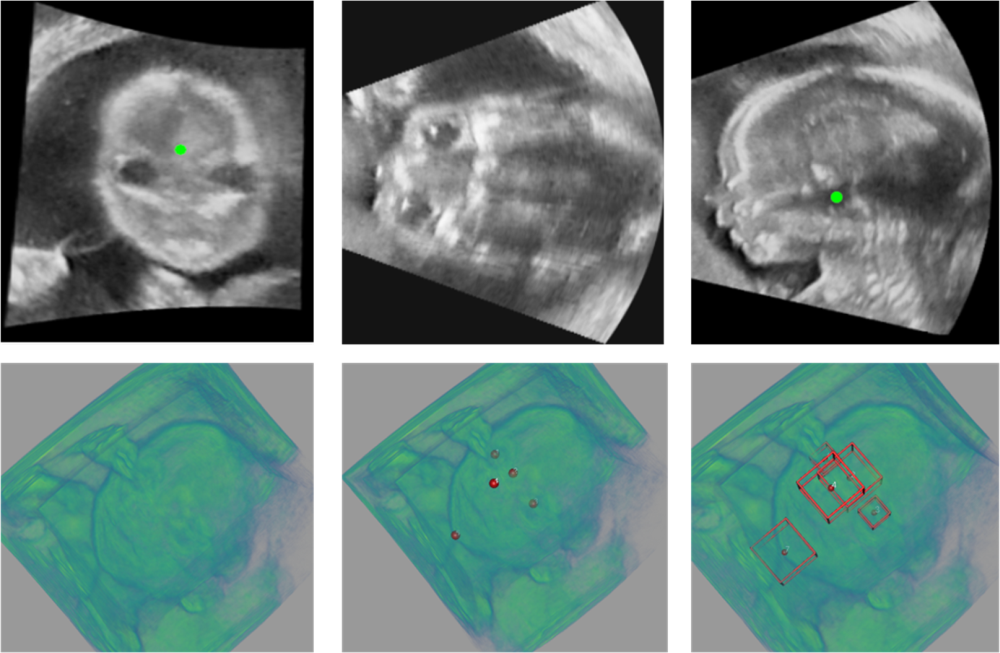

Refer to caption

Fig. 1: 3D US of fetal face. First row: from left to right is the coronal, traverse and sagittal US plane of fetal face. Second row: from left to right is volume rendering of fetal face, 5 fetal facial landmarks and 5 landmark-centered B-boxes.

However, it is not a trivial task. The poor image quality, the presence of speckle and acoustic shadows, and the large volume size of 3D US scans raise problems in designing automated localization methods (Fig. 1). Large pose and size variability of fetuses further increases the difficulty of the task. An ideal landmark detection method needs to localize the target landmarks while recognize each of their classes simultaneously. Some of the existing methods resort to directly regress the spatial coordinates of landmarks [3, 4, 5]. Others used heatmap-matching approaches. For example, Payer et al. [3] proposed a deep neural network to predict the Gaussian heatmap of each landmark. In [1], Huang et al. proposed to formulate the landmark detection as a segmentation task by directly segmenting landmark-centered bounding box (B-box) regions. While being efficient, these models may struggle in learning both the localization and classification (recognize different landmarks) tasks using the same set of parameters, especially in 3D US. Furthermore, these regression methods only provide prediction with the highest confidence, without providing alternatives for further correction.